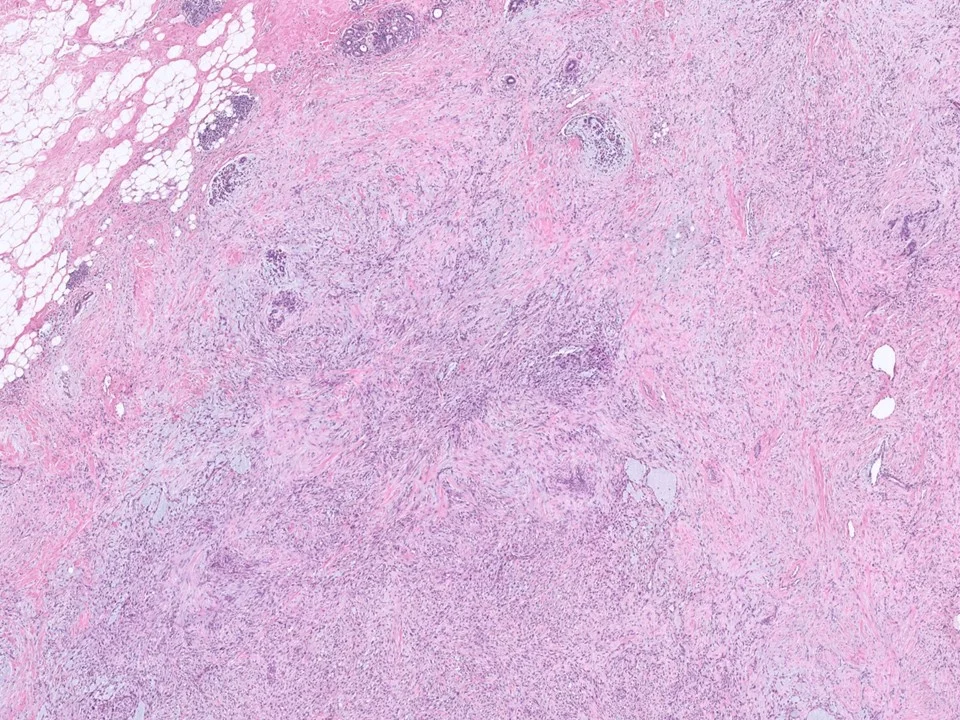

Malignant Phyllodes Tumor

Frond-like projections of cellular stroma covered by epithelium and myopeithelium protruding into epithelial-lined cystic spaces create a leaf-like appearance.

Malignant phyllodes have an infiltrative border (as pictured here), highly cellular stroma, stromal cells with moderate to marked nuclear pleomorphism, and prominent mitotic activity (>/= 10 mits per 10 HPF)